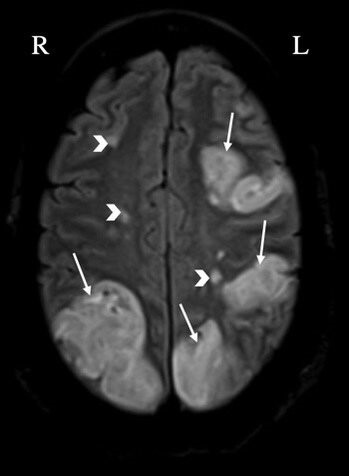

Evidence from computed tomography or magnetic resonance imaging (MRI) of the

brain that are consistent with multiple embolic strokes raise consideration of

NBTE, as detected in a recent patient of ours with NBTE associated with lung

cancer (Fig. 1) [36]. Given the lack of specificity of clinical presentation

alone, brain imaging is often necessary in equivocal cases [37, 38].

Fig. 1.Evidence of multiple bilateral cerebral infarcts in a patient with nonbacterial thrombotic endocarditis (arrows: large infarcts, arrowheads: smaller infarcts) detected by brain magnetic resonance imaging. L, left; R, right.